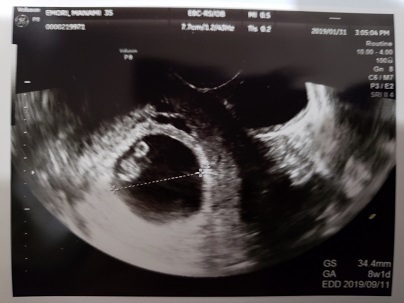

8週0日(8w0d・性別不明)|まなん(´ω`) さん(35歳)

エコー写真撮影時のエピソード:生活面ではニオイでの悪心増悪があり、食事も酸っぱいものを求めるようになったことや長男妊娠中と同じく強い立ちくらみもあり、妊娠かな?と受診したら8週目でした。絨毛膜下血腫があり、自然消失を待ってる状態です。胎児ちゃん自体はエコーで心拍も確認でき、元気な様子でした。このまま大きくなってねと祈りながらエコー映像を見てます。